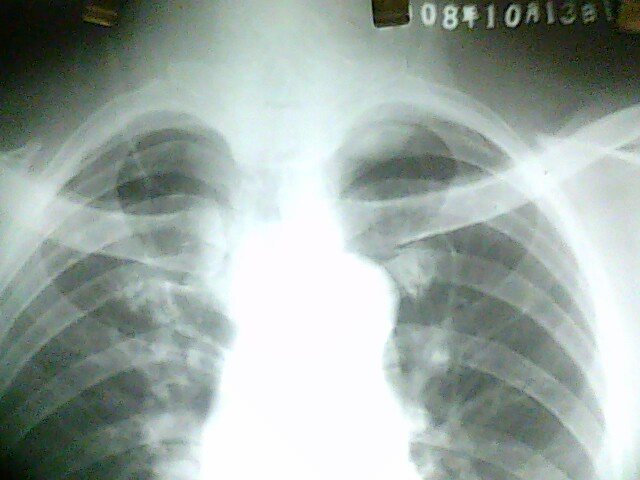

标题: X4925:胸片:男54岁。常规检查

男54岁。常规检查 。给病人透视了一下,这个位置侧位看不到。还是考虑你胸膜病变。已建议ct,有结果我会发上来。

左肺尖病灶:首先考虑肺上沟癌,其次左上纵隔肿瘤。

左上胸膜肿瘤。

没有侧位片,从正位片上可知气管未受压,考虑为来自后纵隔或胸膜的良性肿瘤.

气管似略右移,病变位于主动脉水平以上,首先排除胸内甲状腺

既然是常规检查,肯定没有临床指征,考虑肺顶胸膜局限性增厚,建议ct以除外占位。

这个病人做了ct,追踪时已经出院,没看到结果和片子。病历上写的是:ct报的是左胸廓入口占位,建议颈部和胸部增强扫描。但据说病人不愿意增强,已经出院。